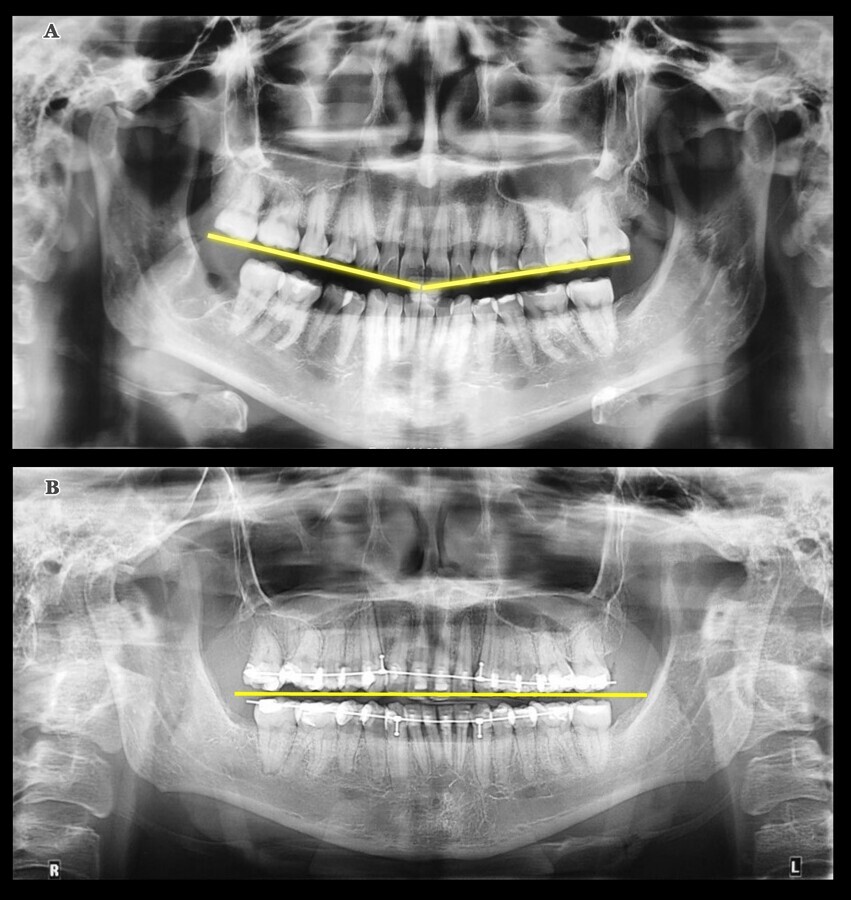

Figura 3. A) Imagen panorámica inicial de la inclinación del plano oclusal. B) Panorámica final que muestra la rectificación del plano oclusal.